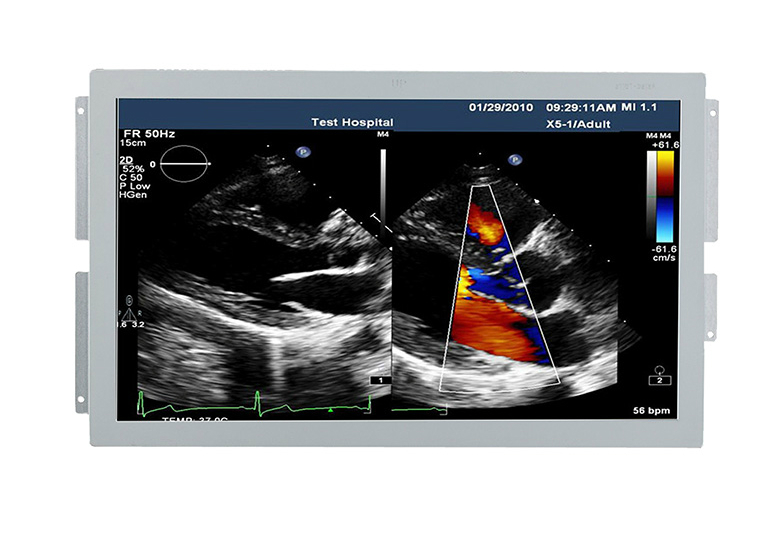

超声医用显示器